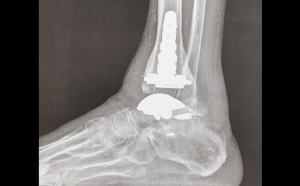

Lesiones osteocondrales grandes del astrágalo:tratamiento primario con autoinjerto de huesoesponjoso y colgajo autólogo de periostio invertido abril 2, 2024 Ver más